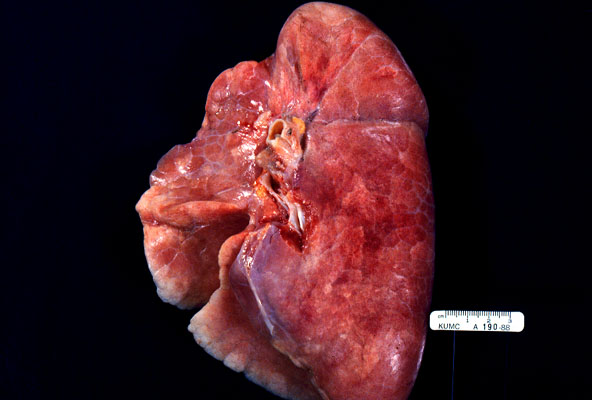

Normal lung, gross

The normal lung at autopsy has a pink color and is well-aerated, whereas a congested lung is red-brown, heavy, and often exhibits pulmonary edema and sub-crepitance (crepitant means you can feel little pockets of air when you squeeze the lung, sub-crepitant means those little pockets are full of fluid).